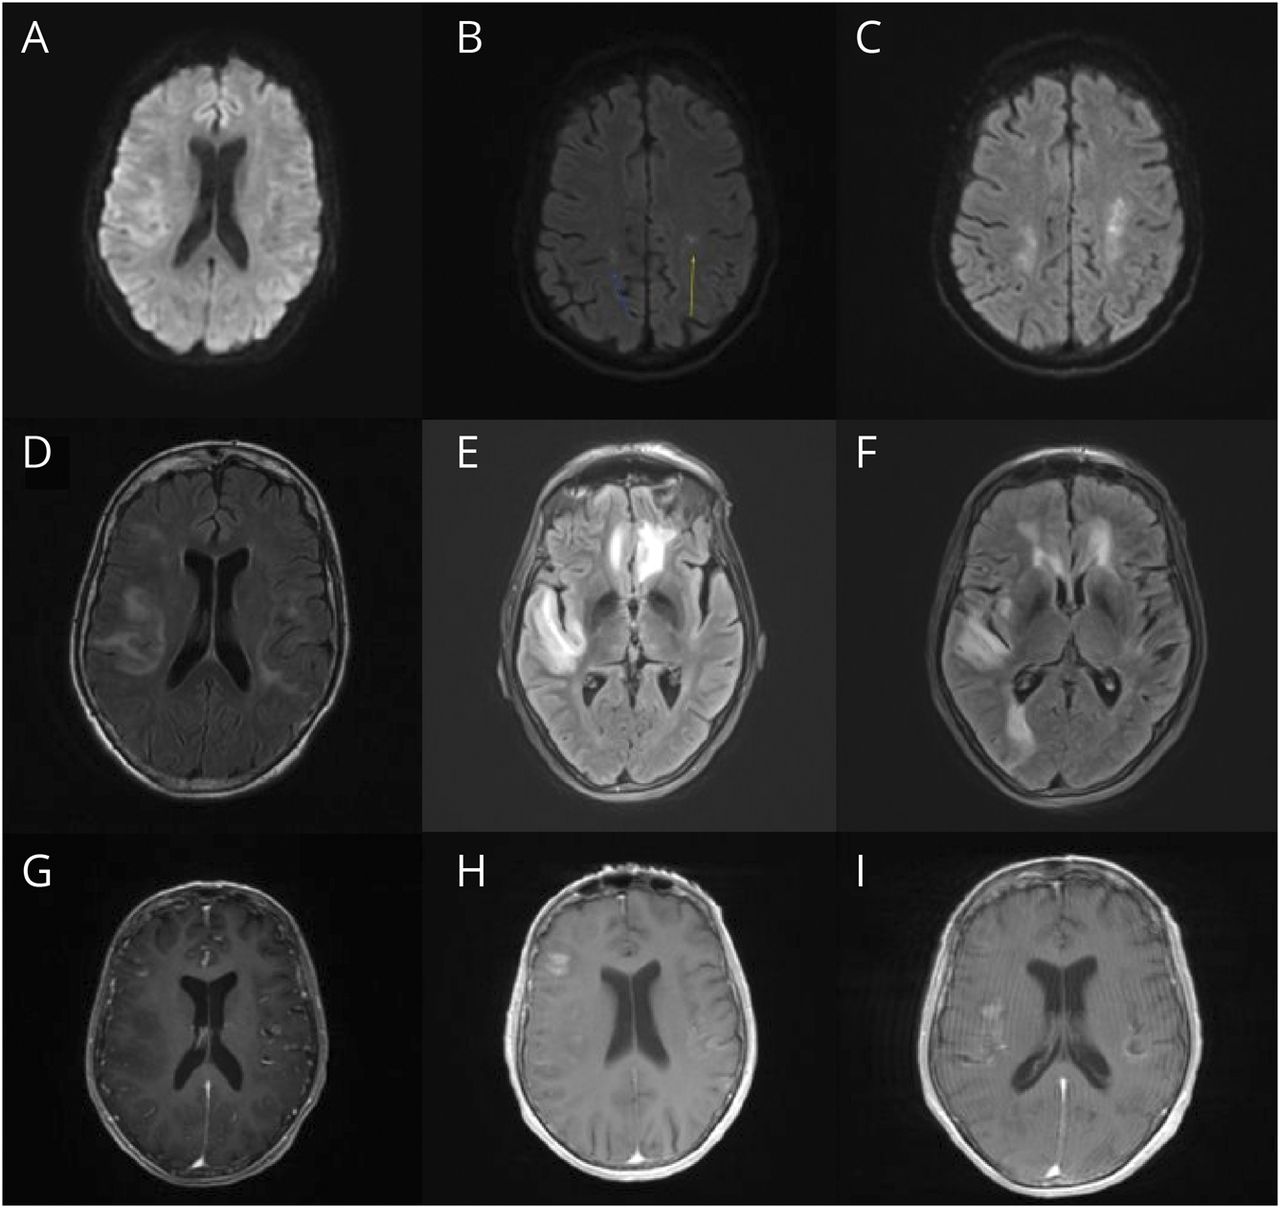

(A - C)第一次(A)、第二次(B)和第三次入路(C)的DWI图像显示扩散受限病灶进展,最终累及双侧额叶、双侧顶叶、右侧枕叶和右侧小脑半球。(D - F)第一次(D)、第二次(E)和第三次入路(F)的T2/FLAIR图像显示,皮层下信号增强主要发生在双侧额顶叶岛叶和外侧颞叶,并逐渐累及双侧直回、双侧额顶叶区、右侧额外侧区、右侧岛叶、右侧颞叶、右侧枕叶和右侧小脑半球。(G - I) T1第一次(G)、第二次(H)和第三次(I)入路造影后图像显示钆增强的进展,最终累及双侧直回、双侧额顶区、右侧额外侧区、右侧岛、右侧颞叶、右侧枕叶和右侧小脑半球。